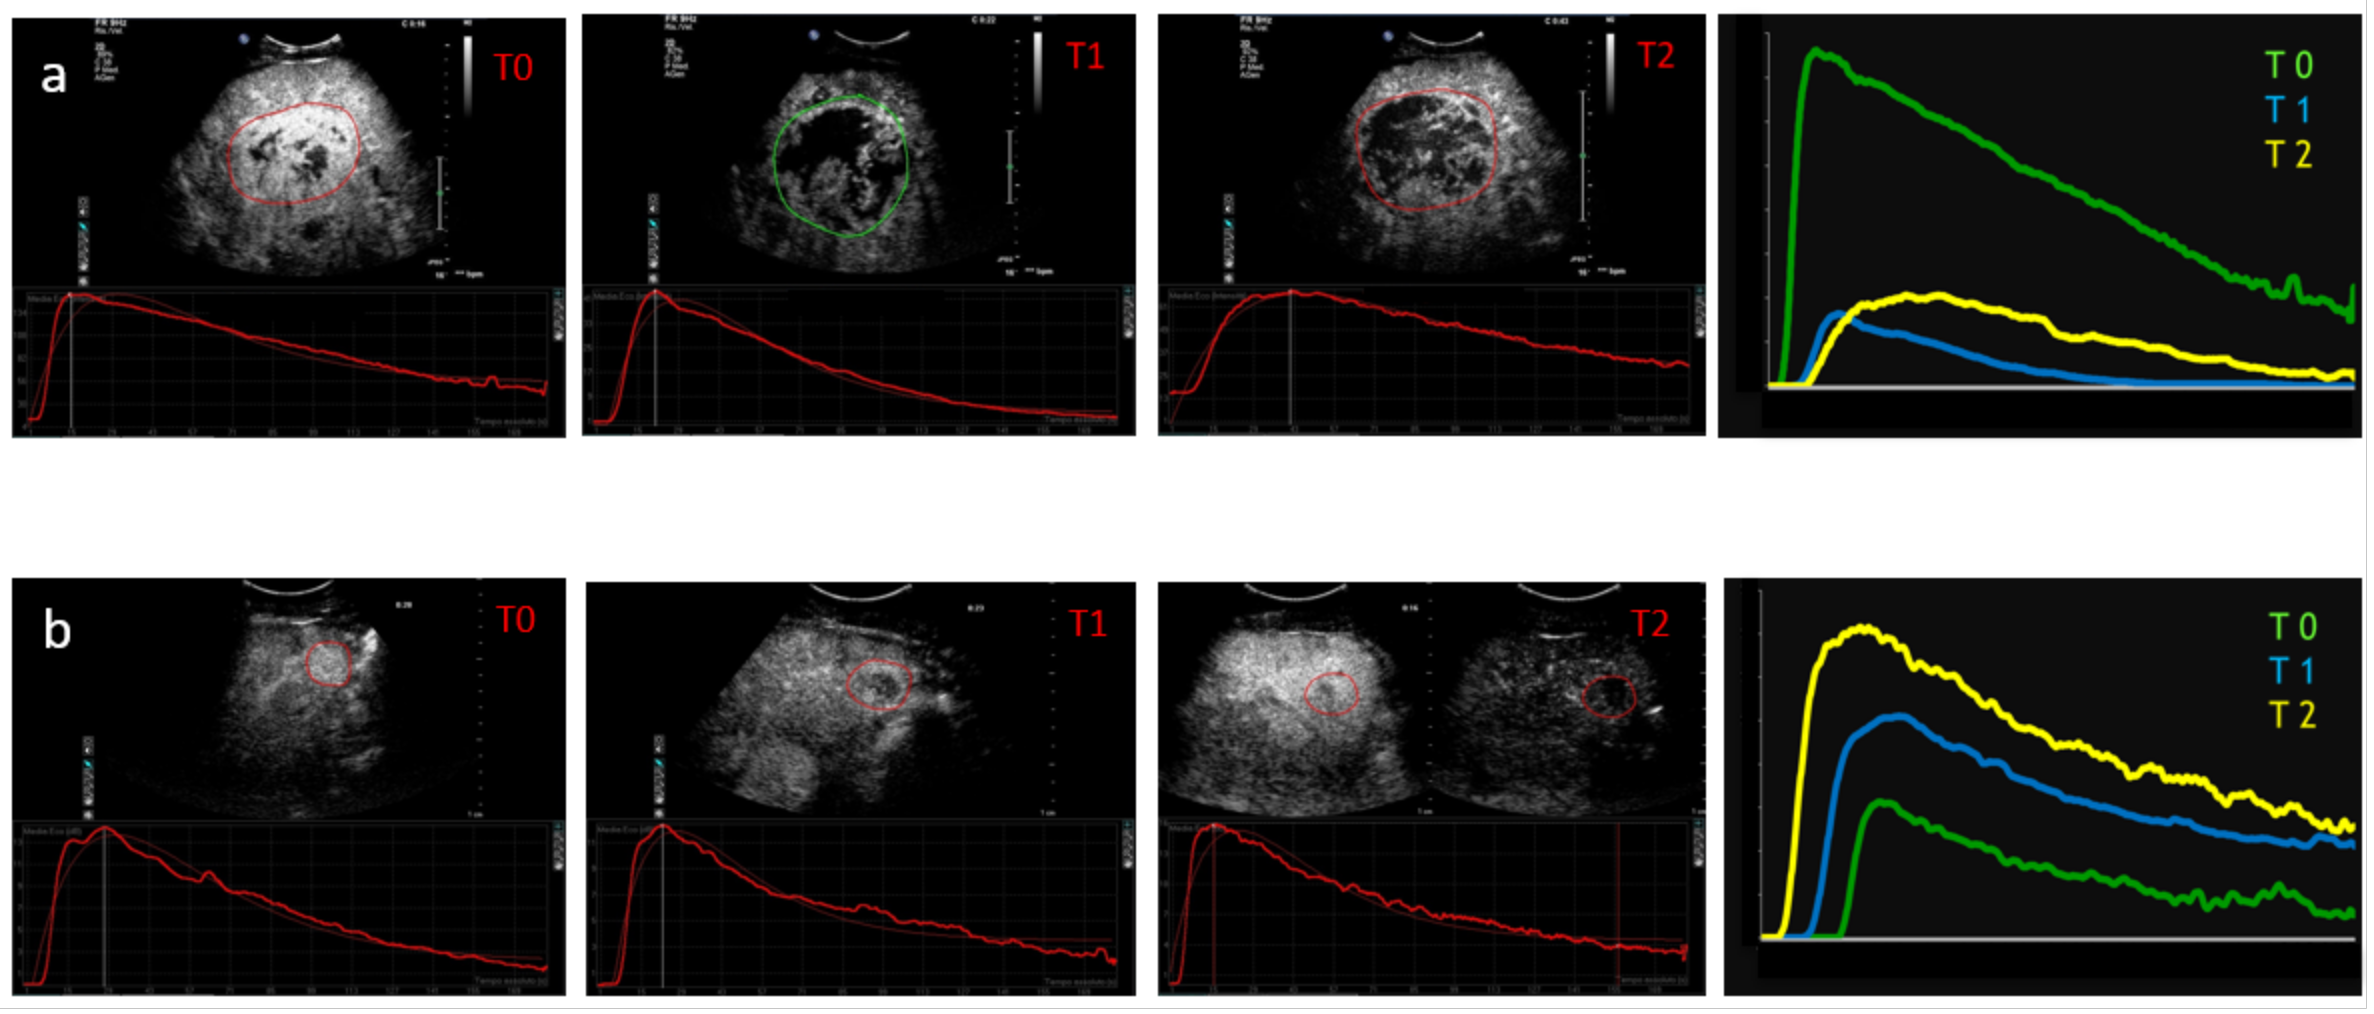

2. Technical Considerations Regarding Dynamic CEUS Application

- Time to peak (TP) is the time from zero intensity (immediately before the contrast arrives in the ROI) to maximum intensity.

- Wash-in time (WIT) is time from 5% intensity to 95% intensity.

- Wash-out time (WOT) is the time from the peak of the curve to the zero value again.

- Peak intensity (PI) is the maximum intensity on the time–intensity curve.

- Mean transit time (MTT) describes the mean time taken by the CEUS bubbles (from the time of first arrival in the ROI) to pass through the ROI. Mathematically it is the first moment of the TIC curve. This parameter is easily calculated from the fitted mathematical model and is often given in a closed-form analytical expression.

- Area under the curve (AUC) is the area under the time–intensity curve above baseline and is calculated numerically between the starting time and a predefined end time. This parameter may be related to blood volume.

- Han, X.; Dong, J.; Liu, Z.; Wu, B.; Tian, Y.; Tan, H.; Cheng, W. Quantitative dynamic contrast-enhanced ultrasound to predict intrahepatic recurrence of hepatocellular carcinoma after radiofrequency ablation: A cohort study. Int. J. Hyperth. 2020, 37, 1066–1073. [Google Scholar] [CrossRef]

- Gao, Y.; Zheng, D.Y.; Cui, Z.; Ma, Y.; Liu, Y.Z.; Zhang, W. Predictive value of quantitative contrast-enhanced ultrasound in hepatocellular carcinoma recurrence after ablation. World J. Gastroenterol. 2015, 21, 10418–10426. [Google Scholar] [CrossRef]

- Sugimoto, K.; Moriyasu, F.; Saito, K.; Rognin, N.; Kamiyama, N.; Furuichi, Y.; Imai, Y. Hepatocellular carcinoma treated with sorafenib: Early detection of treatment response and major adverse events by contrast-enhanced US. Liver Int. 2013, 33, 605–615. [Google Scholar] [CrossRef] [PubMed]

- Zocco, M.A.; Garcovich, M.; Lupascu, A.; Di Stasio, E.; Roccarina, D.; Annicchiarico, B.E.; Riccardi, L.; Ainora, M.E.; Ponziani, F.; Caracciolo, G.; et al. Early prediction of response to sorafenib in patients with advanced hepatocellular carcinoma: The role of dynamic contrast enhanced ultrasound. J. Hepatol. 2013, 59, 1014–1021. [Google Scholar] [CrossRef] [PubMed]

- Wang, Z.; Liu, G.; Lu, M.D.; Xie, X.; Kuang, M.; Wang, W.; Xu, Z.; Lin, M.; Chen, L. Role of portal vein tumor thrombosis in quantitative perfusion analysis of contrast-enhanced ultrasound of hepatocellular carcinoma. Ultrasound Med. Biol. 2015, 41, 1277–1286. [Google Scholar] [CrossRef]

- Kuorda, H.; Abe, T.; Fujiwara, Y.; Okamoto, T.; Yonezawa, M.; Sato, H.; Endo, K.; Oikawa, T.; Sawara, K.; Takikawa, Y. Change in arterial tumor perfusion is an early biomarker of lenvatinib efficacy in patients with unresectable hepatocellular carcinoma. World J. Gastroenterol. 2019, 25, 2365–2372. [Google Scholar] [CrossRef] [PubMed]